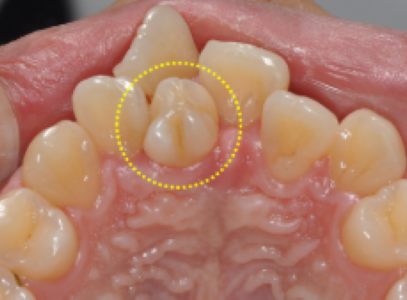

수내교정치과 / 과잉치 - 치료 가이드 & 치료 사례